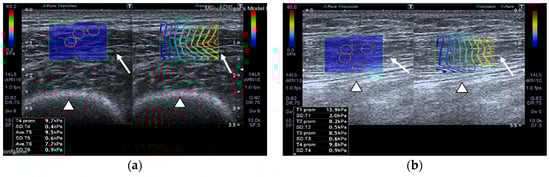

SWE images of a case and a healthy control are shown in Figure 1.

Quadriceps rectus femoris (QRF) muscle ultrasound (US) scan and shear wave elastography (SWE) with several regions of interest (ROIs) (pink circles) measured across the muscle of a matched healthy control (63 years old). SWE shows high muscle elasticity. (a) Transversal QRF muscle (arrow) US scan, femur (arrowhead); (b) longitudinal QRF muscle (arrow) US scan, femur (arrowhead). Patient with multiorgan failure (67 years old). SWE shows muscle stiffness with several regions of interest (ROIs) (pink circles). (c) Transversal QRF muscle (arrow) US scan, femur (arrowhead); (d) longitudinal QRF muscle (arrow) US scan, femur (arrowhead).